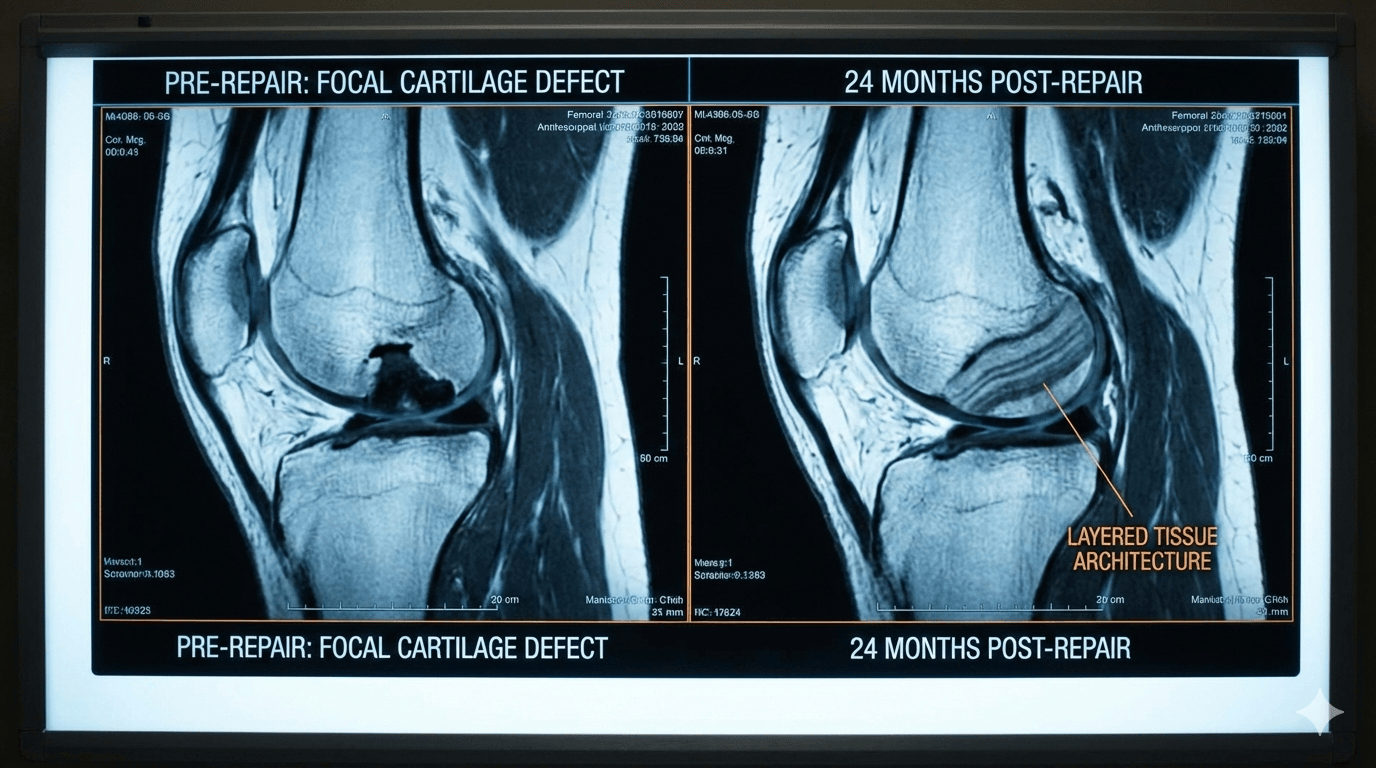

The data, published in the peer-reviewed journal Cartilage, analyzed patients 24 months after receiving GelrinC, a cell-free, off-the-shelf scaffold.

Using the MOCART (Magnetic Resonance Observation of Cartilage Repair Tissue) scoring system—a validated methodology accepted by the FDA and EMA—researchers found a mean score of 88.8 out of 100.

Critically, the MRI results revealed a "layered architecture" comparable to native hyaline cartilage, suggesting the treatment provides a biological restoration rather than the weaker, fibrotic "filler" tissue common in traditional surgeries.